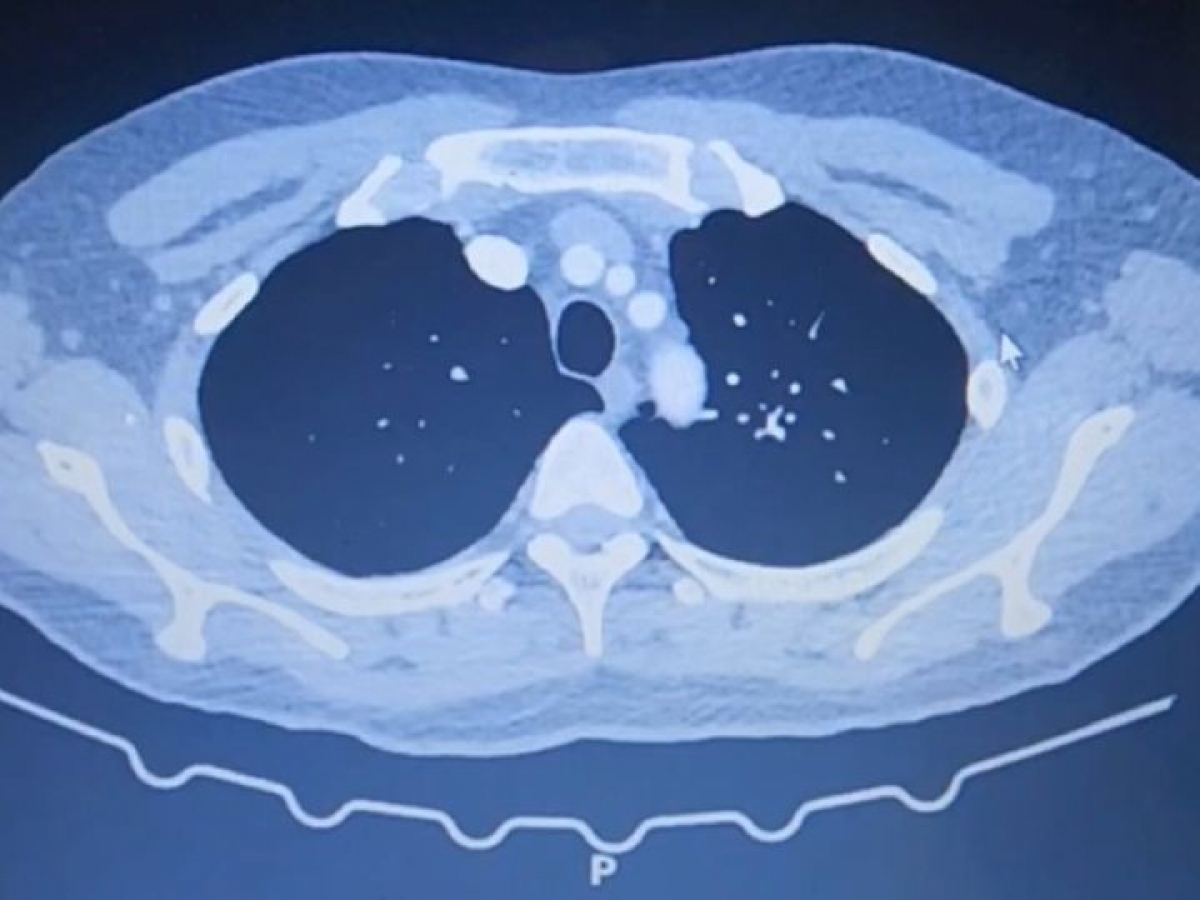

Tại đây, bệnh nhi phải thở máy, bơm surfactant (chất ngăn ngừa xẹp phế nang, giúp chức năng phổi hoạt động ổn định), nuôi dưỡng tĩnh mạch hoàn toàn.

Các bác sĩ nhanh chóng hội chẩn liên khoa và quyết định phẫu thuật cấp cứu cho bệnh nhi để giải phóng khối thoát vị, khâu lỗ thủng ruột. May mắn, ca mổ diễn ra thành công.

| Phương pháp phẫu thuật đòi hỏi sự tỉ mĩ của các bác sĩ |